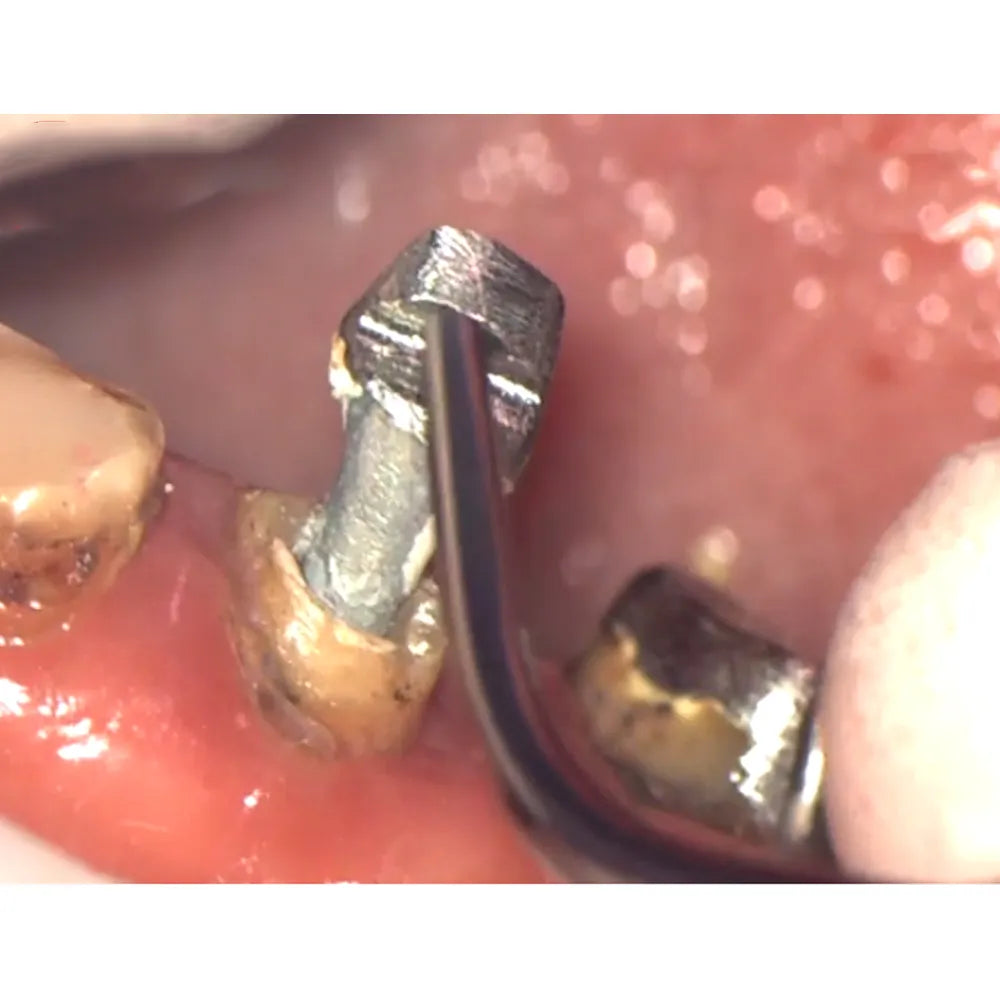

The Woodpecker Scaler Tip GD8 for DTE & Satelec Scalers is a high-efficiency ultrasonic tip designed specifically for the removal of difficult prosthetic parts such as posts. Its advanced ultrasonic technology ensures precise and efficient removal, making it ideal for dental professionals handling complex restorative procedures. The GD8 tip effectively delivers high-frequency vibrations that loosen and dislodge posts and other challenging prosthetic elements with minimal risk of damage to surrounding tooth structures. This tip enhances precision and efficiency during procedures, ensuring a smoother and more controlled removal of prosthetic parts, even in hard-to-reach areas.

- High-efficiency ultrasonic tip for removing difficult prosthetic parts, such as posts

- Functionality: Ultrasonic removal of difficult prosthetic parts, like posts

- Positioning: Apply the tip directly to the prosthetic post or part requiring removal. Use a steady hand to maintain control and precision

- Activate the Tip: Activate the scaler and gradually increase pressure while holding the tip on the post. Maintain pressure until the ultrasonic vibrations successfully loosen and remove the prosthetic part